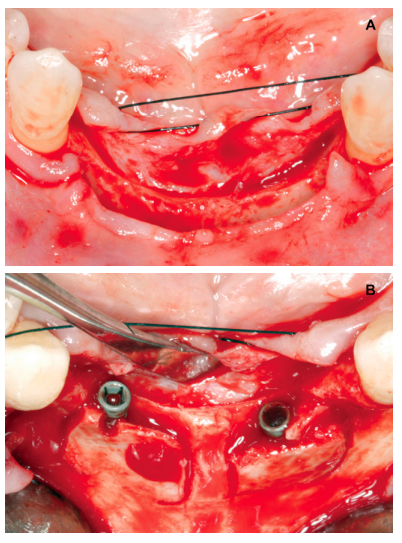

Anitua E, Begoña L, Orive G. Controlled ridge expansion using a two-stage splitcrest technique with ultrasonic bone surgery. Implant Dent 2012; 21: 163-70.

Anitua E, Begoña L, Orive G. Two-stage split-crest technique with ultrasonic bone surgery for controlled ridge expansion: a novel modified technique. Oral Surg Oral Med Oral Pathol Oral Radiol Endod 2011; 112: 708-10.